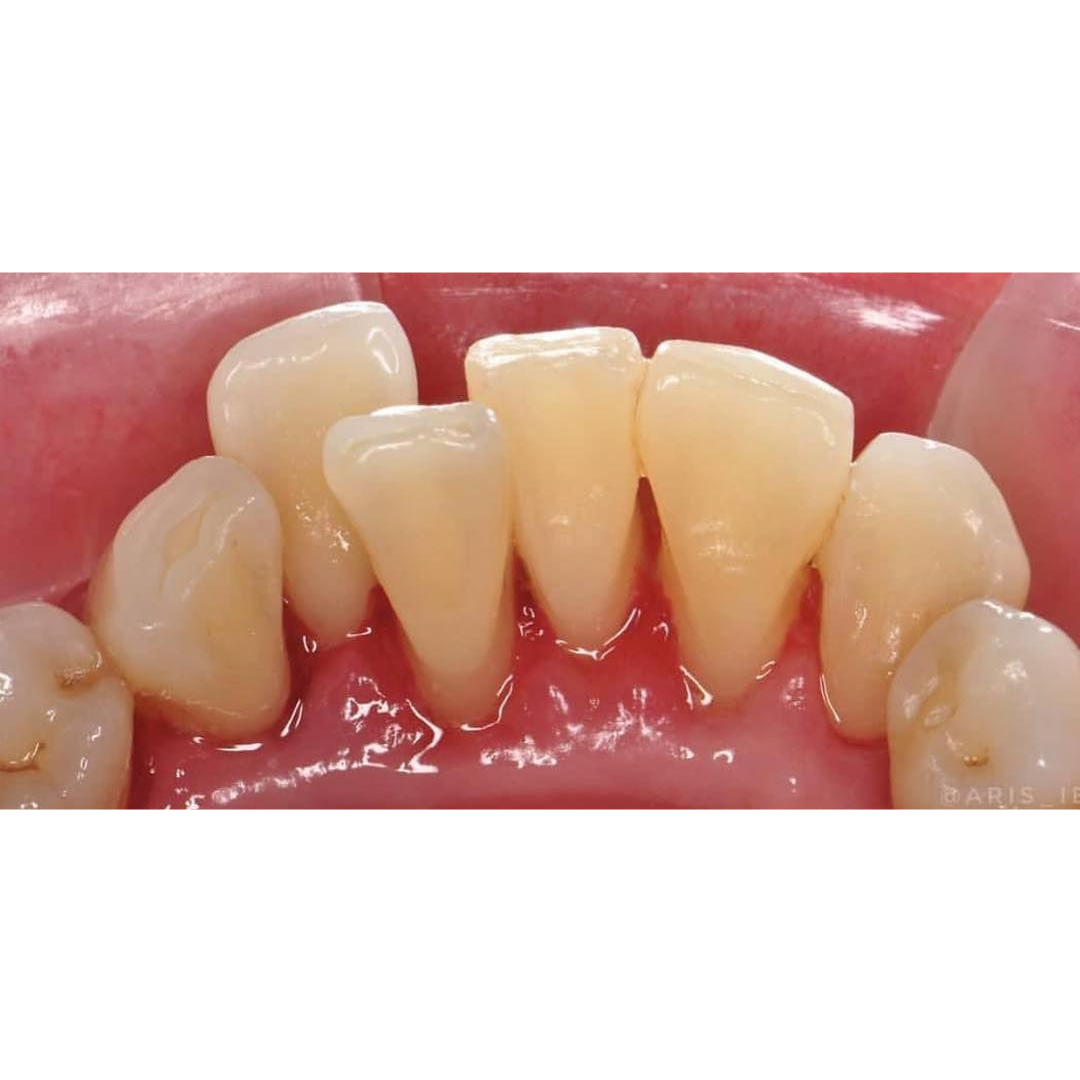

Before & After

📸 Before & After: Scaling Results

From Dental Fear to a Confident Smile

- After scaling, teeth are polished, leaving surfaces smoother and making it harder for plaque to stick again. The result: cleaner, shinier, and healthier-looking teeth.